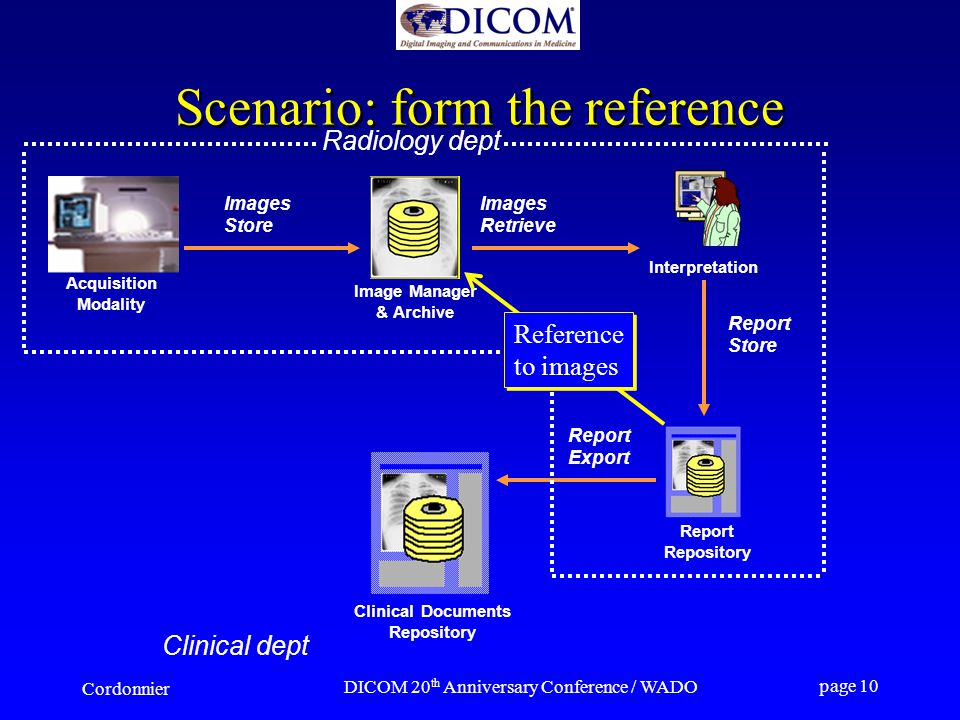

Лазерная камера сетевая для печати изображений на пленке стандарт dicom